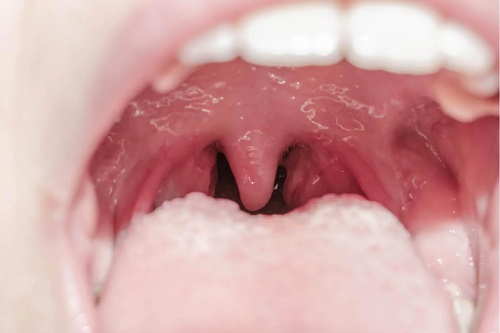

Cauzele, diagnosticul și tratamentul uvulitei

Uvulita este inflamația uvulei, un mic mușchi fusiform agățat de palatul moale (partea din spate a tavanului gurii). Procesele infecțioase, reacțiile alergice, leziunile după anumite intervenții medicale sau consumul de substanțe inadecvate sunt cauzele obișnuite ale uvulitei. Dacă vrei să afli cauzele, diagnosticul și tratamentul uvulitei, citește mai departe!

Potrivit Institutului Național al Cancerului (NCI), uvula este partea moale a țesutului care atârnă în spatele gurii (la marginea palatului moale). Deși experții credeau că această structură este vestigială, au descoperit că are o funcție clară: ajută la prevenirea pătrunderii alimentelor în cavitatea nazală.

Site-ul medical Medigraphic definește uvulita ca „o celulită acută a uvulei, provocând eritem, edem, durere și febră”. Merită menționat faptul că, deși infecțiile bacteriene sau virale sunt cel mai frecvent factor declanșator al acestei afecțiuni, acestea nu sunt singurele.

Pacientul ar trebui să suspecteze această afecțiune atunci când uvula este umflată în comparație cu faringele și are febră. Unele dintre cele mai frecvente simptome sunt următoarele: